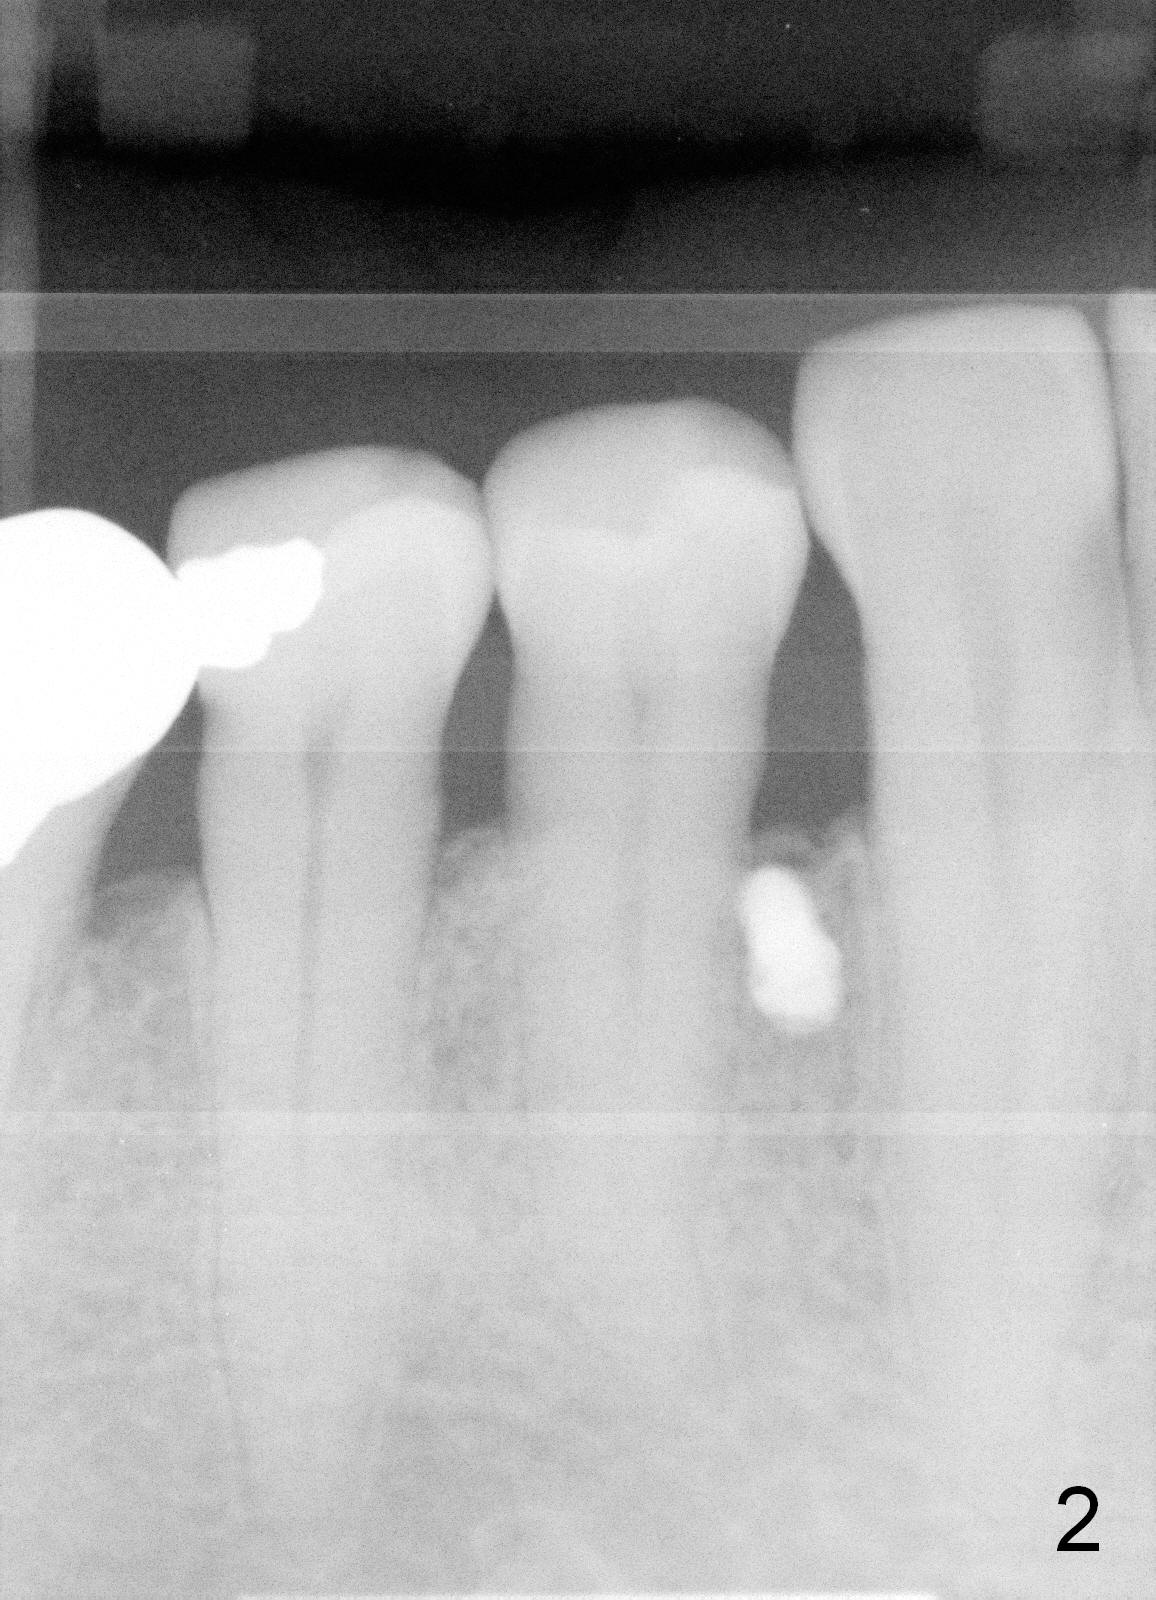

The first two times of mini-implant placement is done without incision or pilot drill. The third time, a vertical incision is made between the teeth #27 and 28 after minimal buccal injection. A pilot drill is placed just coronal to the mucogingival junction (MGJ). It quickly become unstable. An exploration shows that the lingual half of the bone is soft and tender, probably entering the previous osteotomy. Therefore the pilot drill has to be moved slighly apical to MGJ. After penetration of the buccal cortex by the drill, a 1.6x6 mm mini-implant is placed initially (Fig.1). Then the trajectory is changed away from the tooth #28, while the implant is placed deeper. There is great resistance before the implant is fully placed (Fig.2). The patient feels mild discomfort lingually, but there is no sign of lingual plate penetration. Postop, the contact between #28 and 29 is tightened. Cross arch retraction starts immediately.